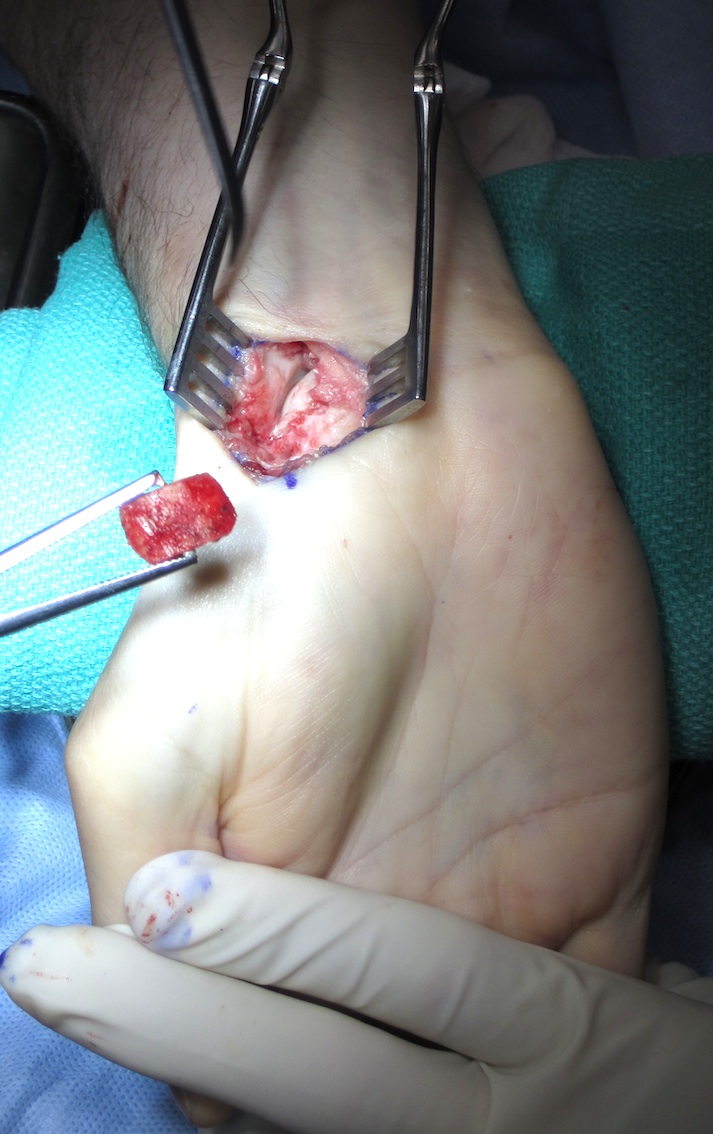

Volar approach

- clean fracture site of fibrous tissue

- osteotomes to reduce deformity

- do not disrupt dorsal cortex

- burrs if needed to remove fibrotic tissue

Assess for AVN

- look for evidence of punctate bleeding from distal fragment

Place bone graft

- reduce deformity if necessary

- fix with K wire

- place cannulated screw